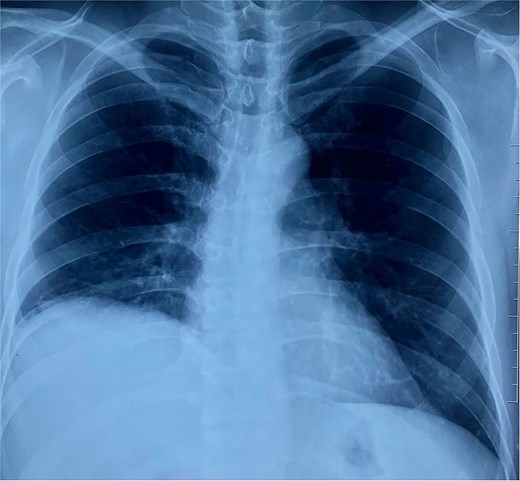

On physical examination, vital signs were stable, and there were no abnormalities. Blood tests and abdominal ultrasound were normal. Gastroscopy shows no lesions. Chest X-ray shows an elevated right hemidiaphragm (Fig. 1). Computed tomography (CT) scan revealed a discontinuity of the right diaphragmatic muscle near the chest wall, with an ~9 × 5 cm hernia defect. This defect established communication between the peritoneal fat and the right pleural space at the lung base (Fig. 2a and b).